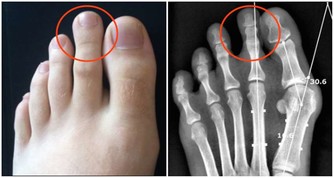

李大爺是一個糖尿病病史十多年的老病友了,平時血糖控制就一般。一個月前的某一天,李大爺從超市買了個泡腳盆回來,當天晚上就興致勃勃的開始了他的“家庭足療”事業。3天后,李大爺突然發現足背有點小破皮,但他並沒有太理會,繼續泡了幾天腳後,才覺得不對勁,傷口越來越大,並且開始紅腫、潰爛。到我們科來就診的時候,李大爺足背的傷口足足有7*5*1cm3(長*寬*深),而且局部紅腫、潰爛,還滲膿液。

李大爺這傷口已經是典型的糖尿病足了,大家都知道一旦得了糖尿病足,潰瘍進展是很快的,而且很難癒合,所以李大爺就因為這傷口在我們科住了半個多月,還沒有痊癒,可以說是“一失足成千古恨”。